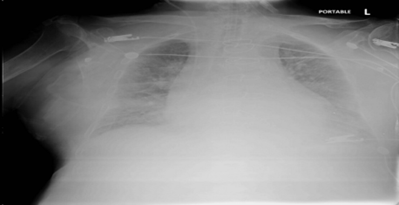

His Chest x ray (Figure 2 ) showed pulmonary edema and cardiomegaly.

Figure 2: Chest x ray showing cardiomegaly and pulmonary edema.